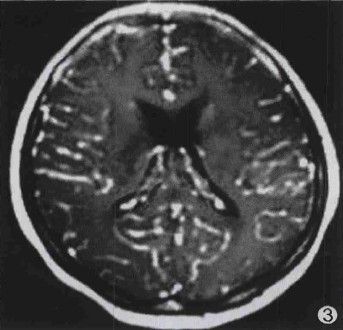

图3 蛛网膜-蛛网膜下腔强化方式为主,同时右额部硬脑膜强化。

2.2 结核瘤并发结核性脑膜炎20例,3例粟粒性脑结核均同时伴有结核性脑膜炎;其中16例基底池脑膜增厚伴基底池闭塞,12例同时伴有环池及侧裂池狭窄或闭塞;4例大脑凸面脑膜增厚,2例伴梗阻性脑积水,7例显示双侧大脑中动脉狭窄。增强扫描示脑膜呈条状、斑块状或结节状强化;3例脑基底部脑膜呈串珠样小结节强化,强化方式以蛛网膜-蛛网膜下腔强化为主;3例同时伴有硬脑膜-硬膜下强化。